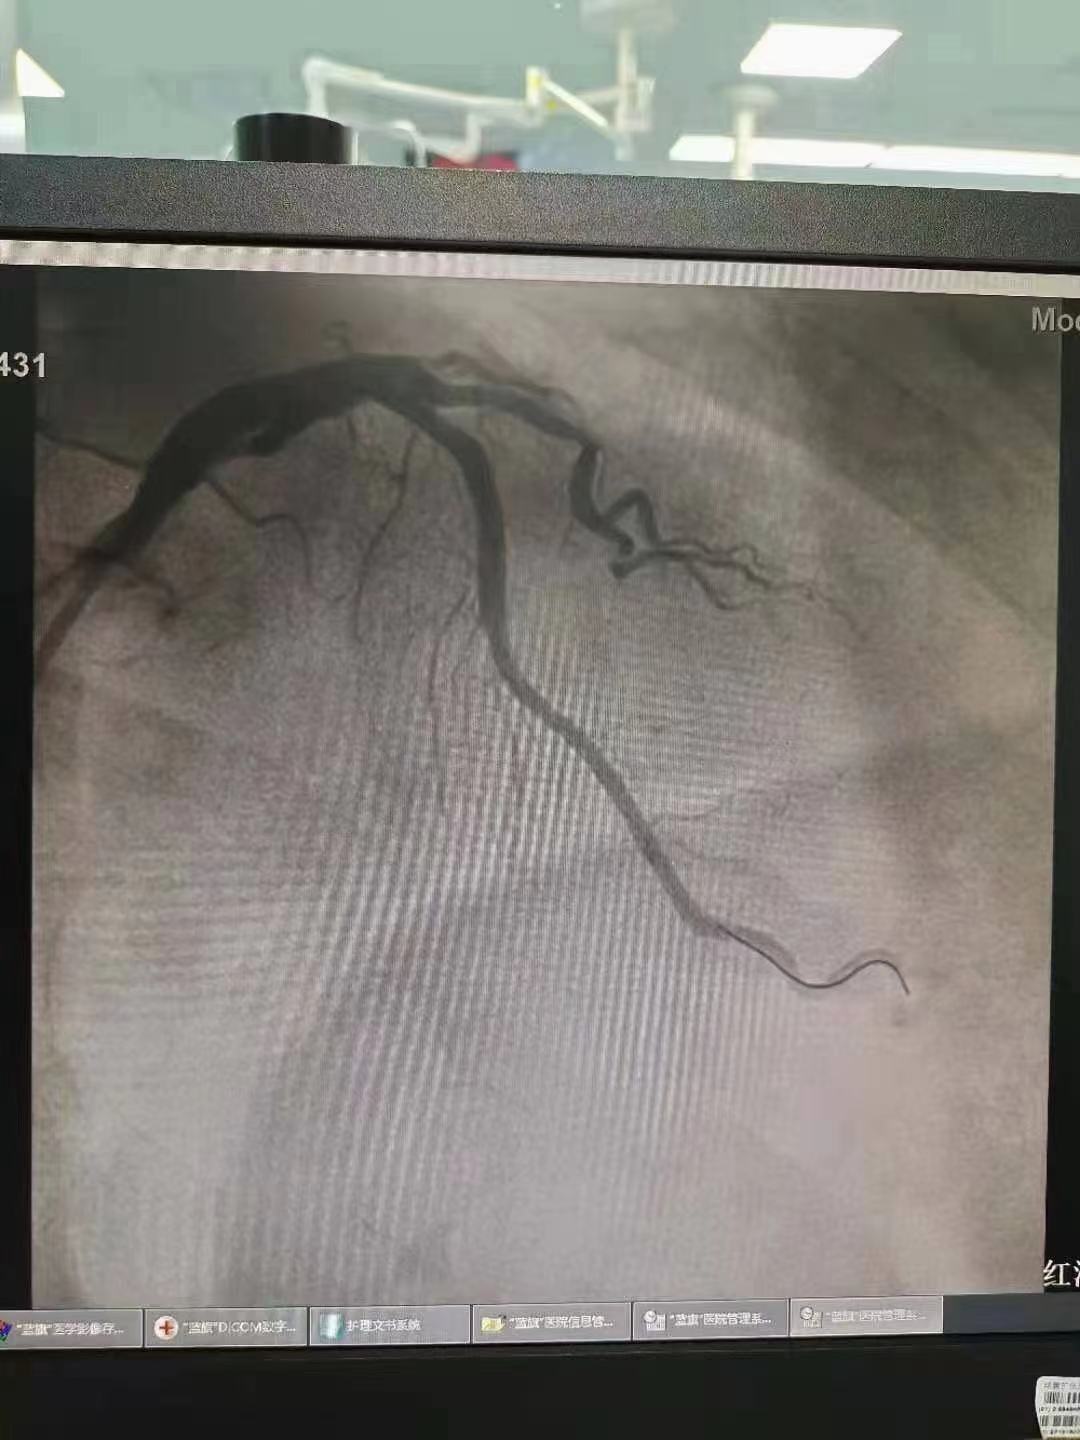

祝賀 云南省滇南中心醫(yī)院  黃銳團(tuán)隊(duì)成功為患者植入3.5~15Xinsorb生物可吸收支架!